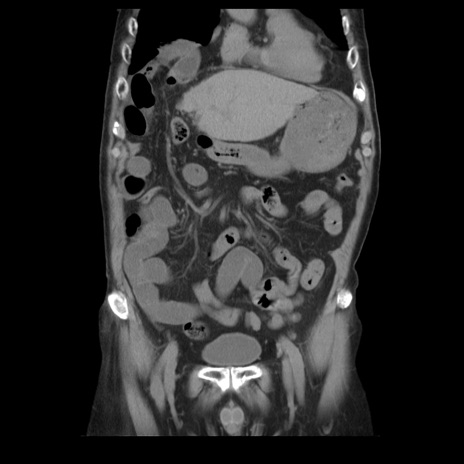

症例21(冠状断像)

【症例】70歳代男性

【主訴】腹痛

【現病歴】肝硬変・肝細胞癌にてかかりつけの方。約9時間前に食後より腹痛出現。症状が徐々に増悪し、嘔吐出現したため来院。

【既往歴】肝硬変、肝細胞癌(RFA、TACE後)

【身体所見】意識清明、表情苦悶様、BT 36℃、BP 129/78mmHg、P 88bpm、SpO2 97%(RA)、右上腹部から心窩部にかけて圧痛あり、反跳痛なし、筋性防御あり。

【データ】WBC 5800、CRP 0.16